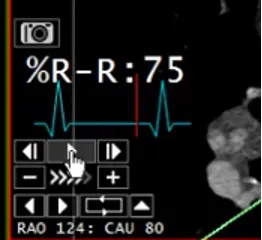

- Hit the play button to see the cardiac cycle

- Can be used to visually assess wall motion and contractile function (within limitation)

- Can be used to assess valve function (e.g. opening and closing)